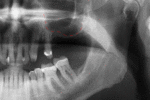

Success or failure of implants depends on the health of the person receiving it, drugs which affect the chances of osseointegration and the health of the tissues in the mouth. The amount of stress that will be put on the implant and fixture during normal function is also evaluated. Planning the position and number of implants is key to the long-term health of the prosthetic since biomechanical forces created during chewing can be significant. The position of implants is determined by the position and angle of adjacent teeth, lab simulations or by using computed tomography with CAD/CAM simulations and surgical guides called stents. The prerequisites to long-term success of osseointegrated dental implants are healthy bone and gingiva. Since both can atrophy after tooth extraction, pre-prosthetic procedures such as sinus lifts or gingival grafts are sometimes required to recreate ideal bone and gingiva.

The long-term success of implants is determined, in part, by the forces they have to support. As implants have no periodontal ligament, there is no sensation of pressure when biting so the forces created are higher. To offset this, the location of implants must distribute forces evenly across the prosthetics they support.[14](pp15–39) Concentrated forces can result in fracture of the bridgework, implant components, or loss of bone adjacent the implant.[15] The ultimate location of implants is based on both biologic (bone type, vital structures, health) and mechanical factors. Implants placed in thicker, stronger bone like that found in the front part of the bottom jaw have lower failure rates than implants placed in lower density bone, such as the back part of the upper jaw. People who grind their teeth also increase the force on implants and increase the likelihood of failures.[6](p201–208)

When a more exacting plan is needed beyond clinical judgment, the dentist will make an acrylic guide (called a stent) prior to surgery which guides optimal positioning of the implant. Increasingly, dentists opt to get a CT scan of the jaws and any existing dentures, then plan the surgery on CAD/CAM software. The stent can then be made using stereolithography following computerized planning of a case from the CT scan. The use of CT scanning in complex cases also helps the surgeon identify and avoid vital structures such as the inferior alveolar nerve and the sinus.[17][18](p1199)

Hard tissue (bone) reconstruction

Bone grafting is necessary when there is a lack of bone. While there are always new implant types, such as short implants, and techniques to allow compromise, a general treatment goal is to have a minimum of 10 mm in bone height, and 6 mm in width. Alternatively, bone defects are graded from A to D (A=10+ mm of bone, B=7–9 mm, C=4–6 mm and D=0–3 mm) where an implant's likelihood of osseointegrating is related to the grade of bone.[26](p250)

An implant is tested between 8 and 24 weeks to determine if it is integrated. There is significant variation in the criteria used to determine implant success, the most commonly cited criteria at the implant level are the absence of pain, mobility, infection, gingival bleeding, radiographic lucency or peri-implant bone loss greater than 1.5 mm.[37]